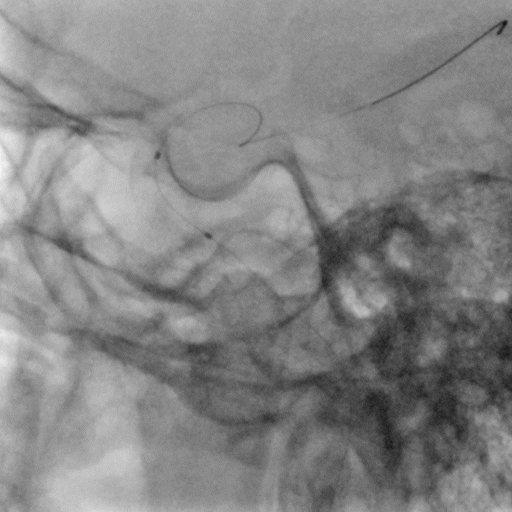

右侧颈动脉系统造影显示:右侧颈内动脉起始段及颅内段未见狭窄;大脑中动脉显影可,远端血流速度可;大脑前动脉显影浅淡,前交通动脉未开放,右侧胚胎大脑后动脉。

左侧颈动脉系统造影显示:颈内动脉开口无狭窄,供血入颅;眼动脉段可见重度狭窄,狭窄率约70%;同侧大脑中动脉及大脑前动脉未见狭窄,前交通动脉开放代偿右侧大脑前动脉供血,左侧后交通动脉未开放。

左侧锁骨下动脉造影显示:左侧锁骨下动脉、椎动脉开口及颅内段均未见异常,基底动脉及各分支显影可。

颅内球囊扩张导管进行球囊扩张。

球囊泄压后造影。

术后造影示无明显残余狭窄,颅内血管无明显栓塞。